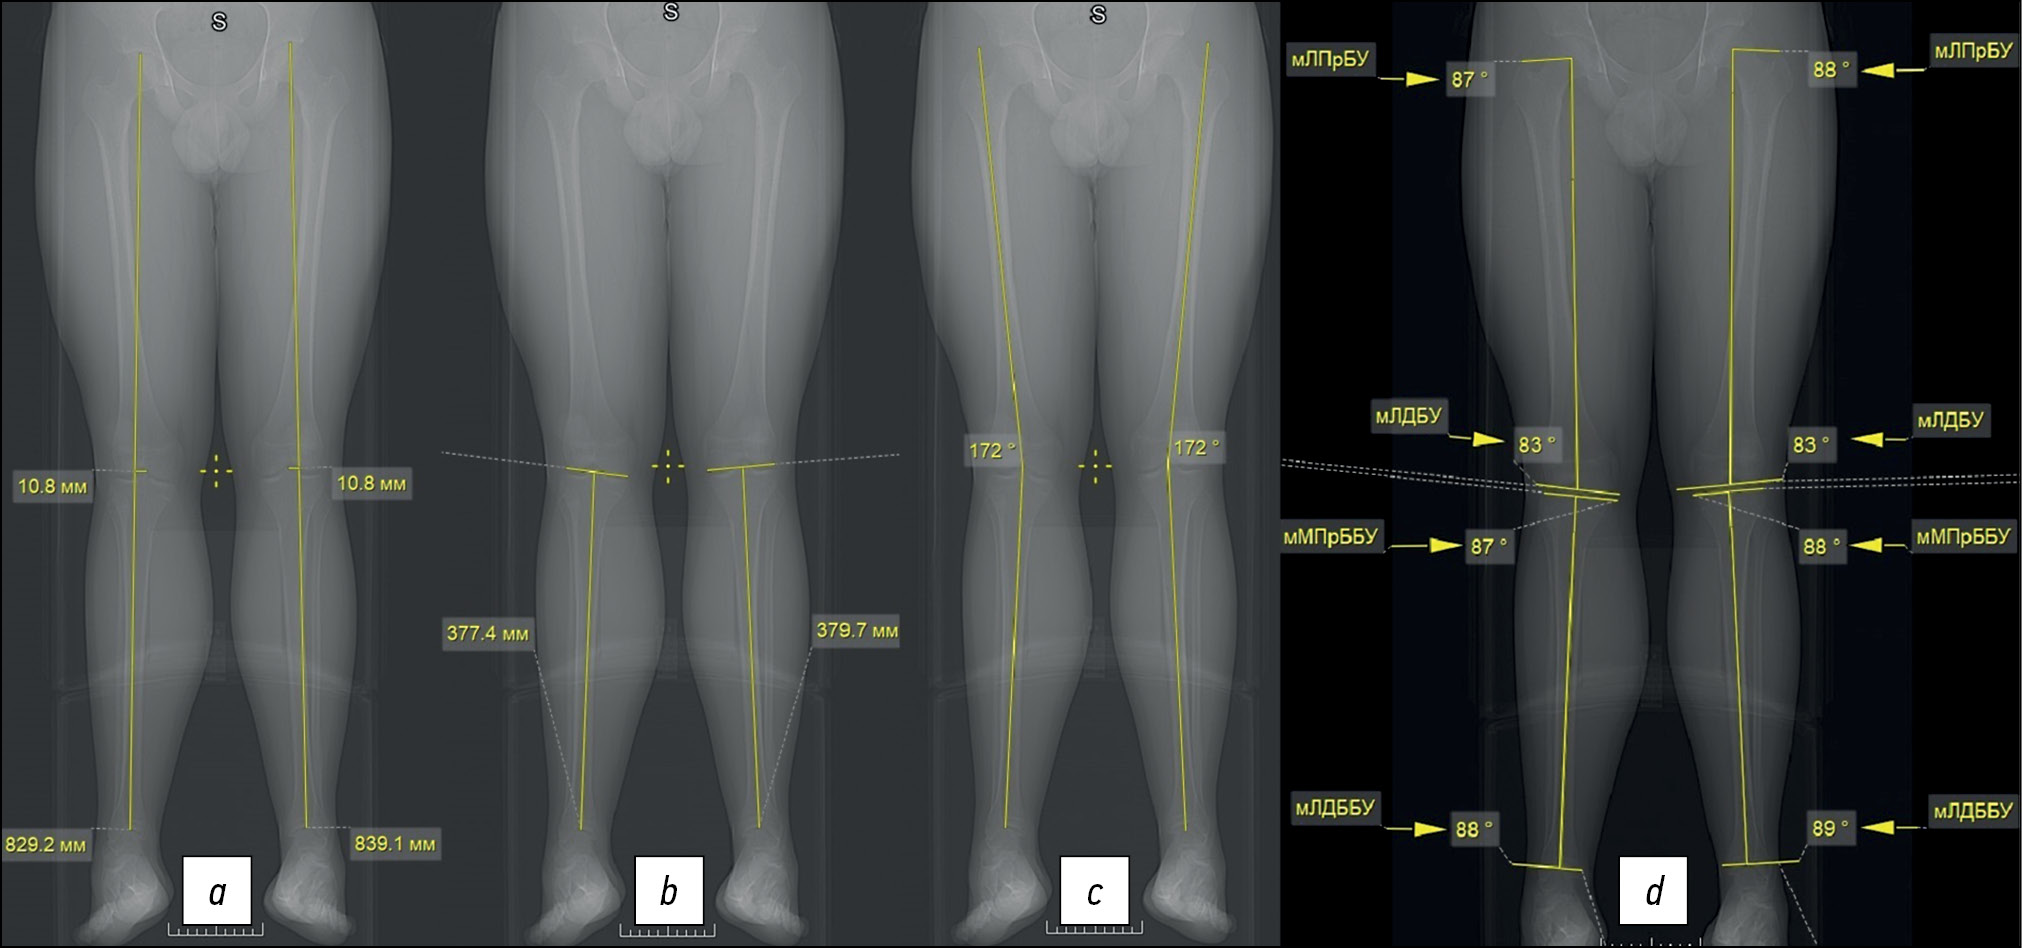

По топограмме МСКТ нижних конечностей в прямой проекции измеряли абсолютную длину нижних конечностей, длину сегмента голени, угол между продольными осями бедренной и большеберцовой кости [5]. Также по топограмме в прямой проекции находили референтные линии и углы во фронтальной плоскости [5–8].

- оценивали расстояние от суставной щели тазобедренного до суставной щели голеностопного сустава (механическая ось нижней конечности), определяли абсолютную длину нижних конечностей (бедро + голень) и отклонение механической оси (рис. 1, а);

- измеряли длину голени от суставной щели коленного до суставной щели голеностопного сустава; длину бедра определяли путём вычитания от общей длины длины голени (рис. 1, b);

- находили угол между продольными (анатомическими) осями бедренной и большеберцовой кости (рис. 1, c);

- определяли механические линии и углы бедренных и большеберцовых костей во фронтальной плоскости (рис. 1, d):

— мЛПрБУ — механический латеральный проксимальный бедренный угол;

— мЛДБУ — механический латеральный дистальный бедренный угол;

— мМПрББУ — механический проксимальный большеберцовый угол;

— мЛДББУ — механический латеральный дистальный большеберцовый угол.

Рис. 1. Топограмма нижних конечностей: а) расстояние от тазобедренного до голеностопного сустава, b) расстояние от коленного до голеностопного сустава, c) угол между продольными осями бедренной и большеберцовой кости, d) механические линии и углы бедренных и большеберцовых костей.

Fig. 1. Topogram of the lower extremities: a) the distance from the hip to the ankle joint, b) the distance from the knee to the ankle joint, c) the angle between the longitudinal axes of the femur and tibia, d) mechanical lines and angles femur and tibia.